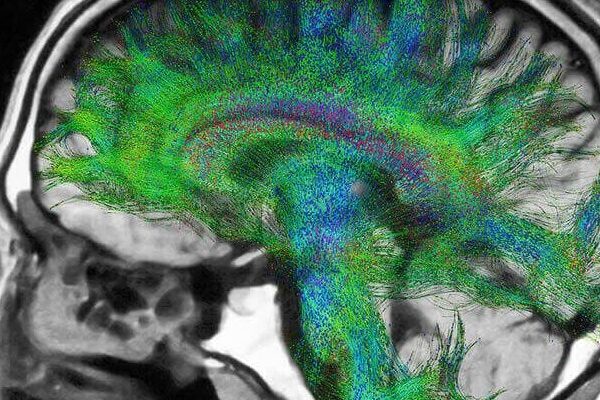

MR Spektroskopi Nedir? MR spektroskopi, beyinde yer alan lezyonların hakkında daha fazla bilgiye erişim sağlayabilmek ve hastaya teşhis koyabilmek adına hastalara uygulanır. Özenle ve özel yapılan emar çekimlerinden biri olarak bilinir. Emar görüntülemesi sayesinde karaciğer, meme ve prostat gibi bölgelerin görüntülemesi yapılır. Burada yer alan kötü huylu kitlelerin tespitinden kullanılır. İleri seviyeli emar olarak bilindiği […]